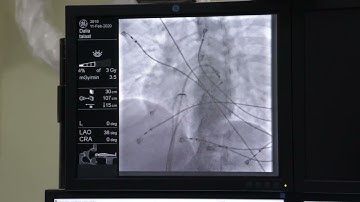

Step by step approach Trans septal puncture with #agilis #EPStudy #AF #ablation